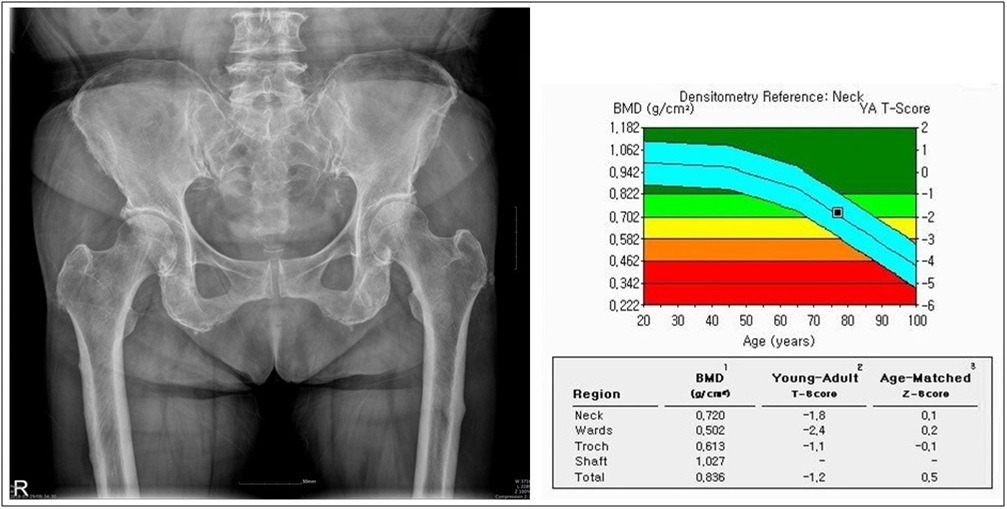

골밀도검사는 뼈 속에 있는 칼슘 등 미네랄의 양을 방사선으로 측정한 결과를 T-score라는 수치로 나타내는데 -1 이하는 ‘골감소증’이라 진단하고, -2.5 이하인 경우 ‘골다공증’으로 진단한다.

Tscore.jpg

문제는, T-score라는 게 건강한 동년배의 뼈와 비교하는 것이 아니라 여성의 일생 중 가장 골밀도가 높은 나이인 '30세 여성의 뼈'와 비교한 수치라는 것이다.